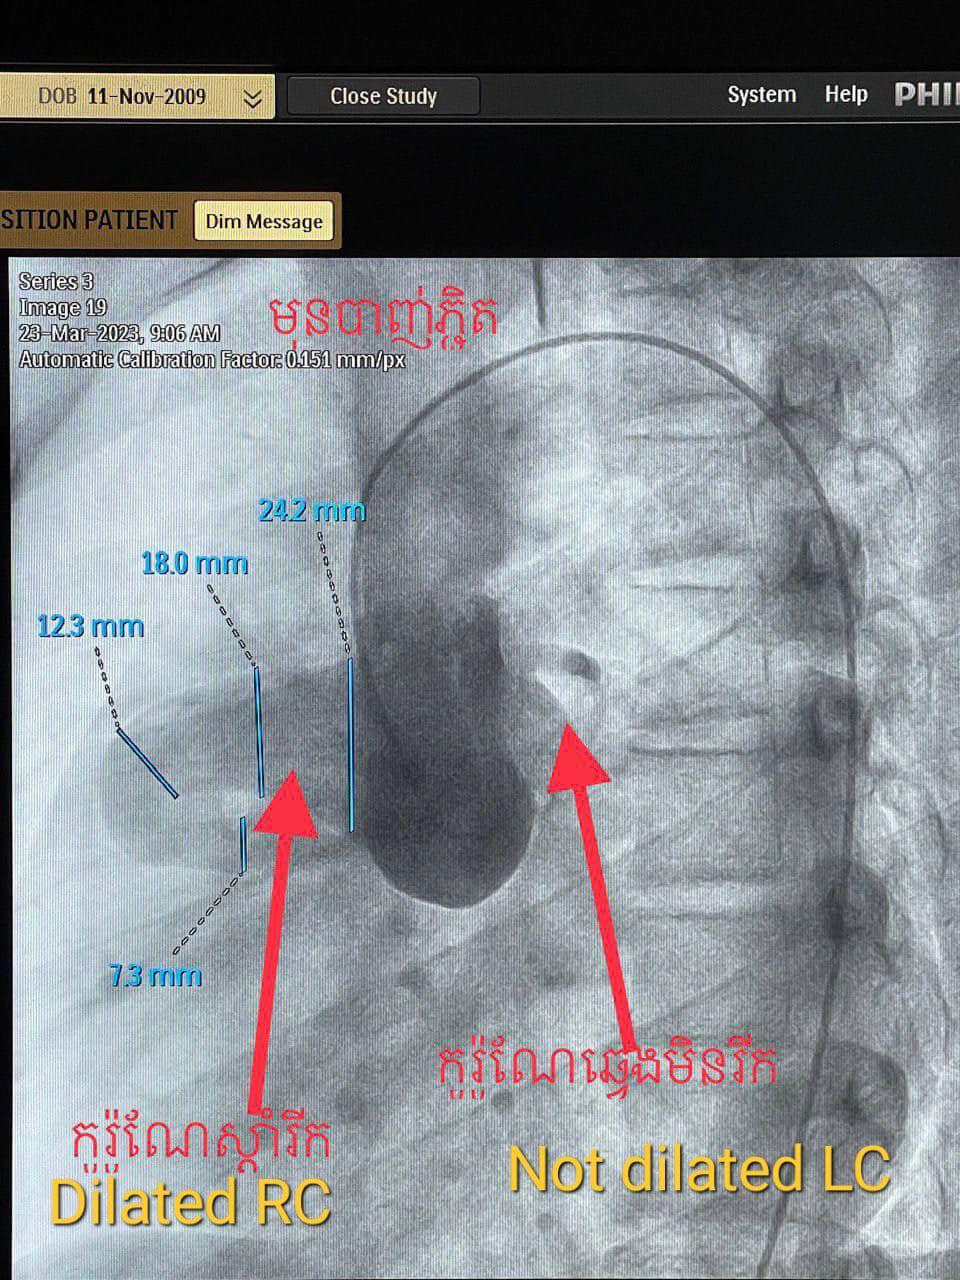

ខេត្តសៀមរាប៖ នៅថ្ងៃទី២៧ ខែមីនា ឆ្នាំ២០២៣ យោងតាមការចុះផ្សាយរបស់ មន្ទីរពេទ្យគន្ធបុប្ផា បានឱ្យដឹងថា ក្មេងប្រុស អាយុ១៣ឆ្នាំ មកពីស្រុកជើងព្រៃខេត្តកំពង់ចាម ដោយអាការៈចុកទ្រូងខ្លាំងរយៈពេល៥ថ្ងៃ ពេលមកដល់មន្ទីរពេទ្យជ័យវរ្ម័នទី៧ គ្រូពេទ្យឯកទេសផ្នែកបេះដូងបានធ្វើរោគវិនិច្ឆ័យយ៉ាងច្បាស់លាស់ថាជាការរីកសរសៃកូរ៉ូណែខាងស្តាំដោយចរន្តឈាមកូរ៉ូណែខាងស្តាំឆ្លងចូលថតបេះដូងស្តាំខាងលើ( RCA fistula to RA)។

ដូចនេះហើយក្រុមវេជ្ជបណ្ឌិតឯកទេសផ្នែកបេះដូងយើងបានរៀបចំដាក់កម្មវិធីបាញ់ភ្ជិតអោយក្មេងប្រុសម្នាក់នេះដោយបច្ចេកទេសទំនើបបំផុតមួយ catheterization to close RCA fistula to RA by vascular plug ប្រកបដោយភាពជោគជ័យ។